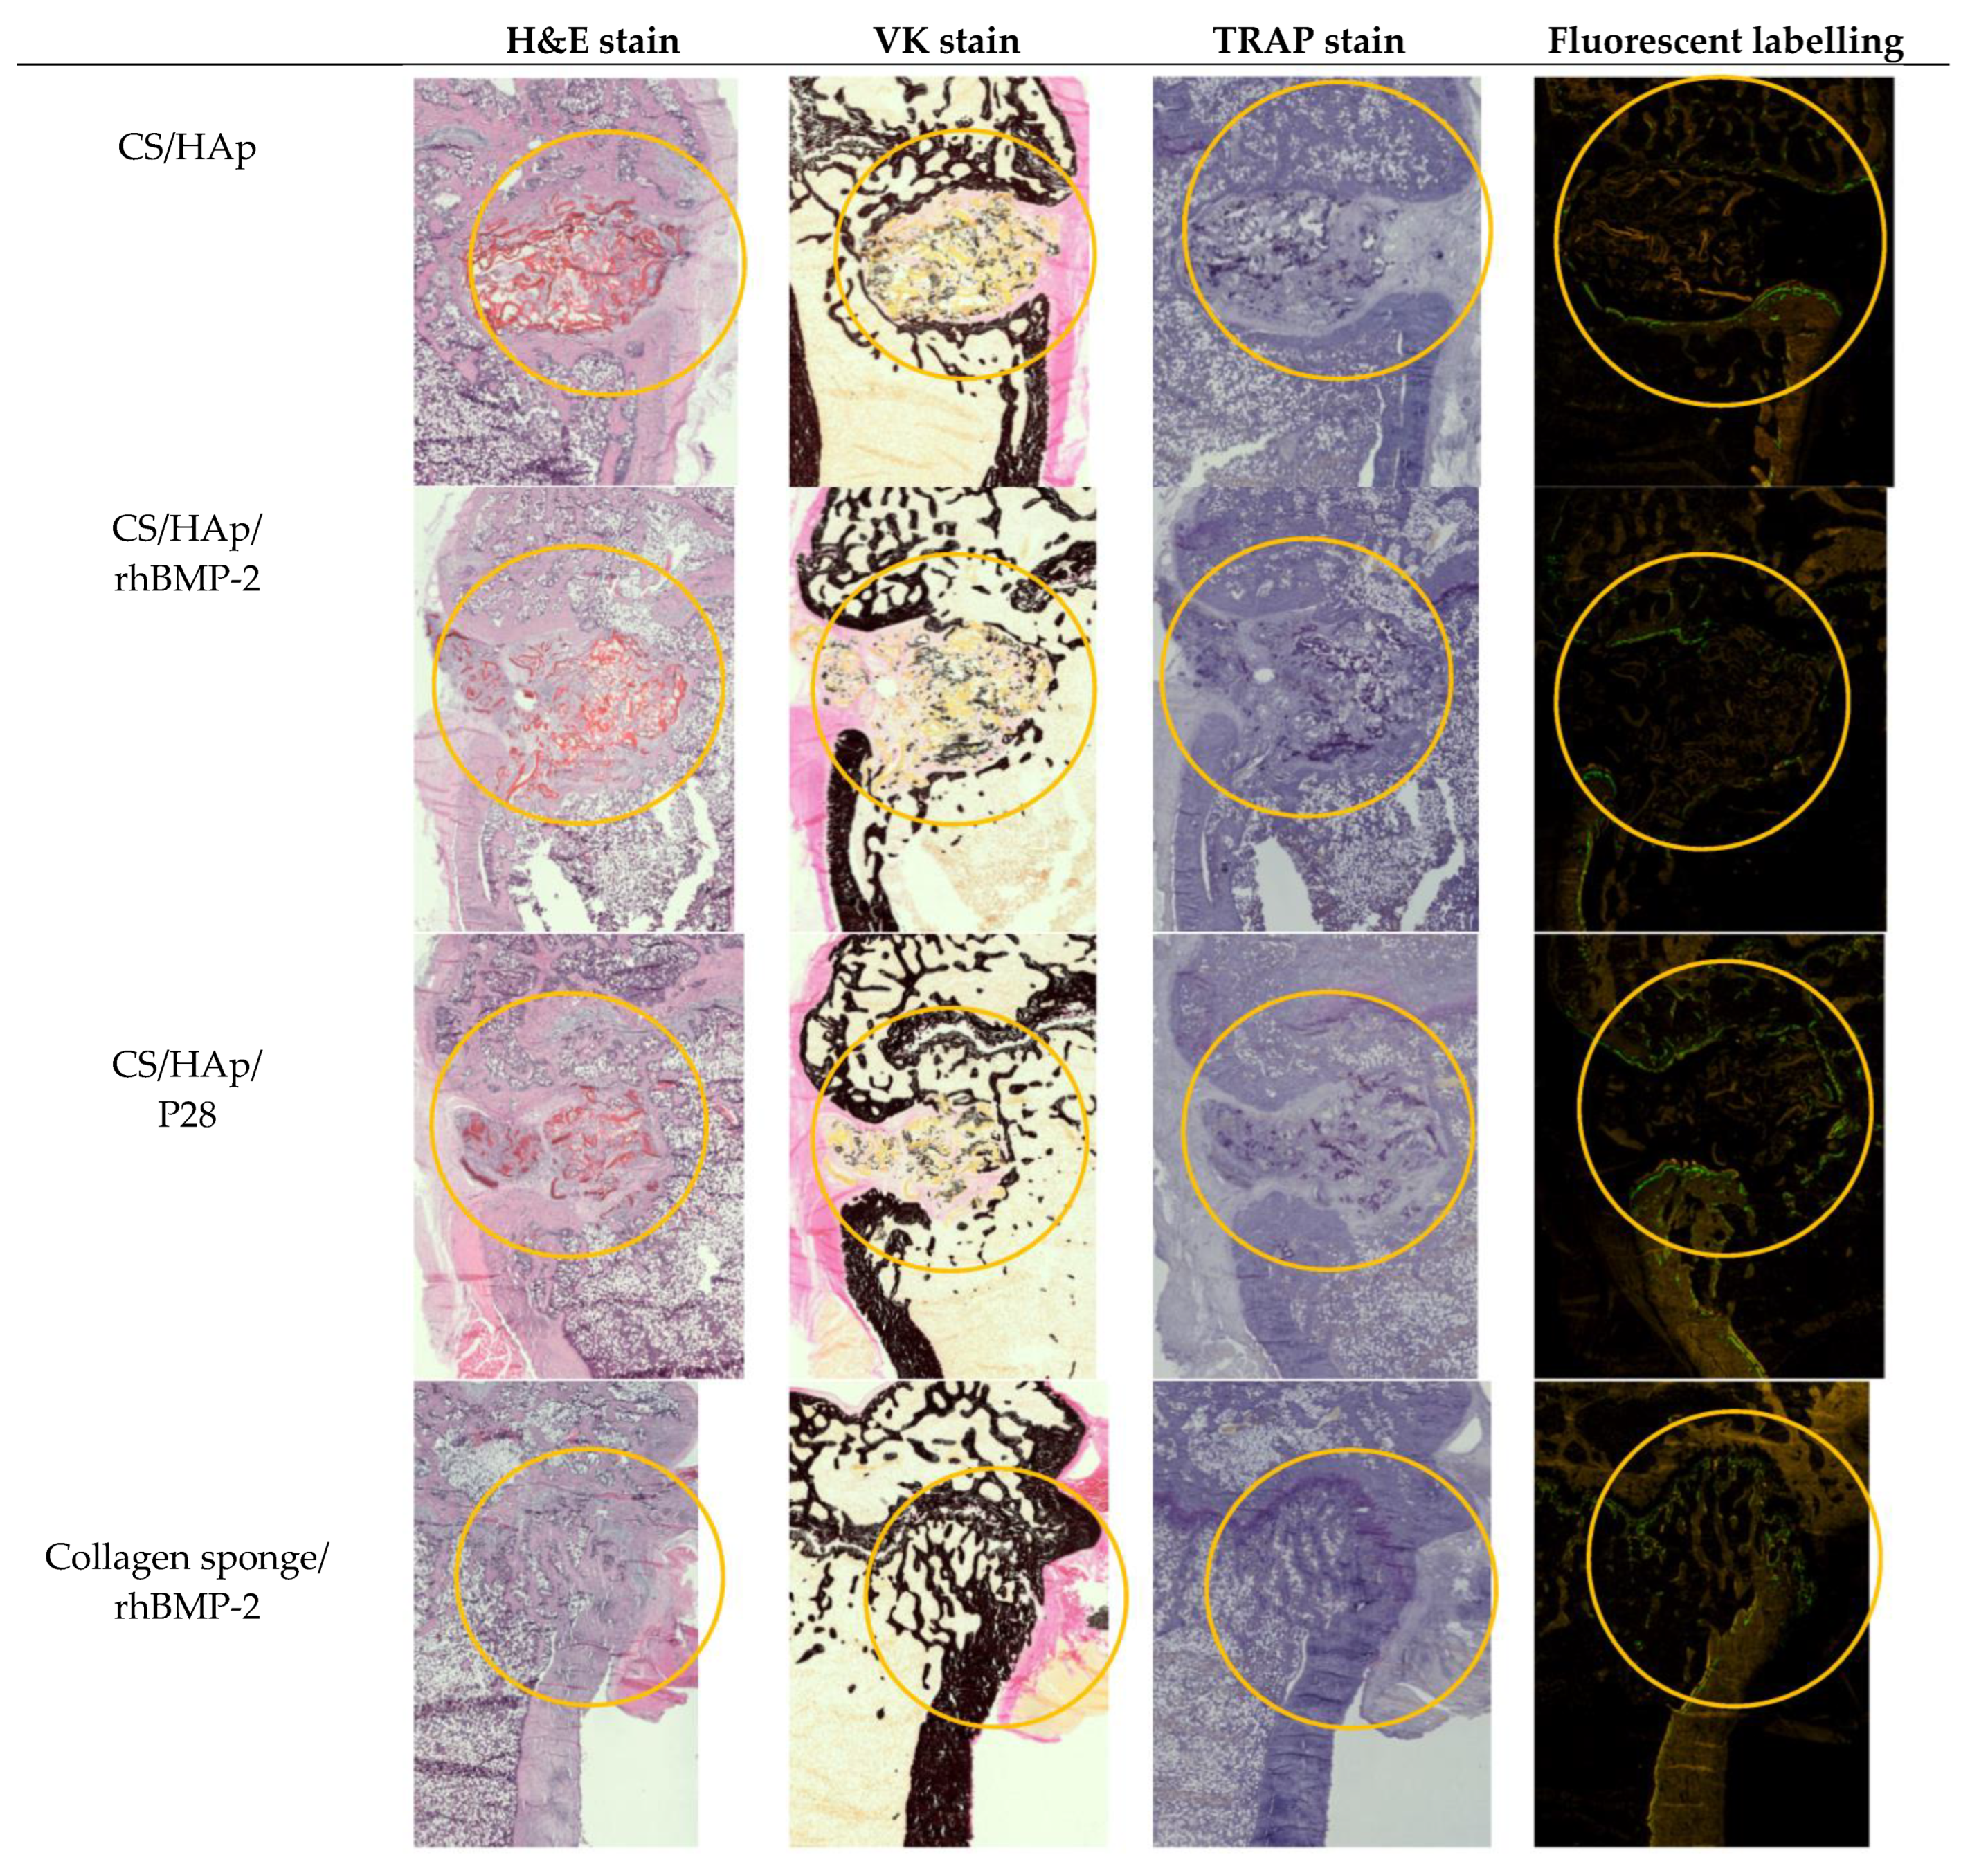

The harvested femoral condyles after eight weeks of healing were embedded in resin blocks and sectioned longitudinally to observe the bone defect in a sagittal view. The overview of the Hematoxylin-Eosin (HE), Von Kossa (VK), Tartrate-Resistant Acid Phosphatase (TRAP), as well as calcein and xylenol fluorochrome labelling, is presented in Figure 10.

Figure 10.

An overview of the HE, VK and TRAP staining as well as the calcein and xylenol fluorescent labelling on the femoral condyles after eight weeks of healing. Observing the defect closure, the CS/HAp/P28 scaffolds presented better bone healing compared to CS/HAp and CS/HAp/rhBMP-2. (Annotation: Yellow circle = Implantation site).

HE staining was carried out for a deep qualitative analysis of the tissues according to ISO10993-6:2016 to assess local tissue changes post-implantation of biomedical devices, where the inflammatory response, tissue morphology, presence of fibrosis, necrosis and some more factors were evaluated [91,92]. In the defect implanted with nude CS/HAp, it can be observed that there was inflammation around the scaffold with some multinucleated giant cells, compared to the defects implanted with CS/HAp/rhBMP-2 and CS/HAp/P28, where there was more resorption observed, and the scaffold had broken down, despite the incomplete degradation. While this inflammation remained low, it was suggested that the CS/HAp scaffold was well tolerated and non-toxic. This result matched the absence of clinical signs during the in vivo phase. In addition, non-anastomosed mature bone lamellae were observed in CS/HAp/P28 scaffolds, suggesting that the P28 peptide can upregulate the osteoblast differentiation and lead to the bone regeneration towards the later stage of hard callus remodelled bone formation [93]. This result was in line with previous work investigating P28 peptides in Si/HAp scaffold, where this peptide provided a significant new bone formation and increased osteoblastic activity compared with nude scaffolds and empty defects [38]. Therefore, it can be postulated that there was a sign of bone formation present that could lead to healing in the long run.

Von Kossa staining was used to stain calcium black, thereby distinguishing between osteoid and mature mineralised bone matrix [94,95]. Sections from the nude CS/HAp scaffold showed signs of remodelling that occurred around the defect margin. Defects implanted with CS/HApp28 and CS/HAp BMP treatments resulted in bone islets been formed around the scaffold, and some calcium could be observed. However, this calcium could also have originated from the scaffold composite itself since hydroxyapatite is composed of calcium [96]. Subsequently, the defects implanted with both collagen sponges with and without BMP-2 seemed to be healed since the cortex was completely intact and the trabecular bone had remodelled that it was not distinguishable from the other side.

The presence of osteoclasts, seen as multinucleated cells under the microscope [97], was evaluated in TRAP-stained slides. Only a few osteoclasts were observed in all implanted materials. In scaffold conditions, osteoclasts were present at the edge of newly formed bone tissue inside the defect and the margin. Some osteoclasts were also observed at the edge of residual mineralised material. This result indicates that the implanted scaffolds can recruit TRAP-positive cells, which might be aided by the rough surface of the scaffolds that support cell attachment and proliferation [98]. Nevertheless, the observed osteoclastic activity could suggest that the bony callus stage of the bone healing process was just initiated [97]. Conversely, fewer osteoclasts were seen in the defects implanted with a collagen sponge compared to the scaffold conditions, which was in line with observations from Vao Kossa staining that indicated that healing and remodelling was near completion.

Fluorochrome labelling indicated the uptake of the labelling agent on the day of injection, thus showing that the bone healing process was ongoing during the injection days. It was observed that double labelling was mainly present along the defect margin in chitosan scaffold-implanted samples, suggesting that the physiological bone remodelling cycle was ongoing at the defect margin [99]. Rare double or single labelling was seen at the surface of mineralised tissue inside the defect, leading to the mineralisation process, which occurred at the new-bone tissue or the residual material surface at that specified time point [100,101]. Therefore, the mineralisation was faster inside the defect when present. In collagen sponge conditions, a few fluorochrome labelling were seen at the bone surface and corresponded only to double labelling suggesting physiological bone remodelling at the bone surface. Double labelling was mainly seen at the bone surface at the defect entrance and was co-localised with osteoid tissue leading to the residual bone formation process at the defect entrance [102].